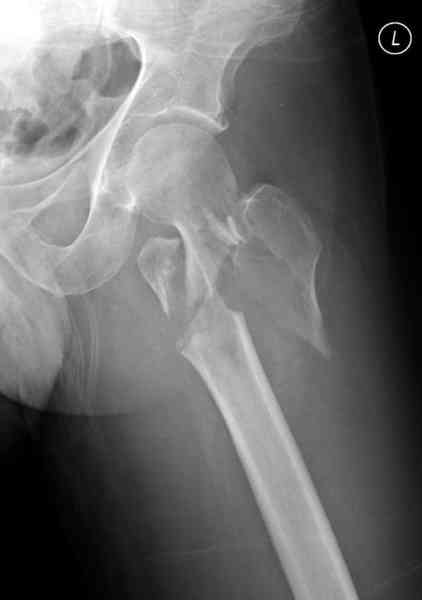

Re: [1/3] Перелом проксимального бедра